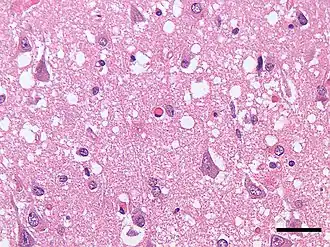

- морфологическое и гистологическое исследование тканей головного мозга (коры, подкорковых ядер) при аутопсии (посмертная диагностика).